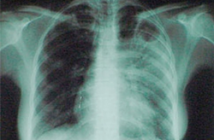

«Никто в Европе на 100 процентов не защищен от устойчивого к лекарствам туберкулеза», - утверждает врач ВОЗ Октай Гозалов.

По данным ВОЗ, в группе риска находятся страны Восточной Европы (Россия и Украина), а также Азербайджан. В Западной Европе самый высокий уровень заболеваемости зафиксирован в Лондоне. Там ежегодно палочка Коха поражает 3,5 тысячи человек, пишет «Газета.Ru».